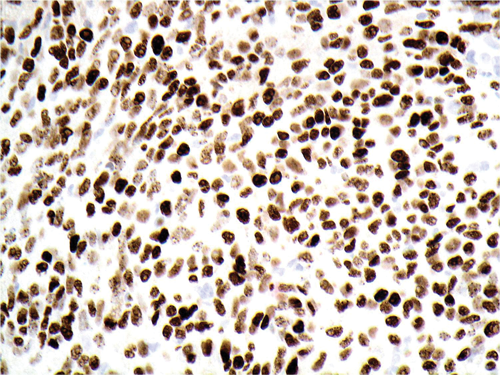

3. Figure 3 is an immunohistochemical stain that is picking out the nuclei of the cells shown in Figures 1 and 2. Which protein is being stained for?

3. Human herpes virus 8 (HHV8).

4. This is Kaposi’s sarcoma.

5. This patient had AIDS secondary to HIV infection (hence the oral candida infection and generalised lymphadenopathy). Highly active anti-retroviral therapy is widely available worldwide and this has lead to diminishing rates of Kaposi’s sarcoma and other HIV associated morbidities.